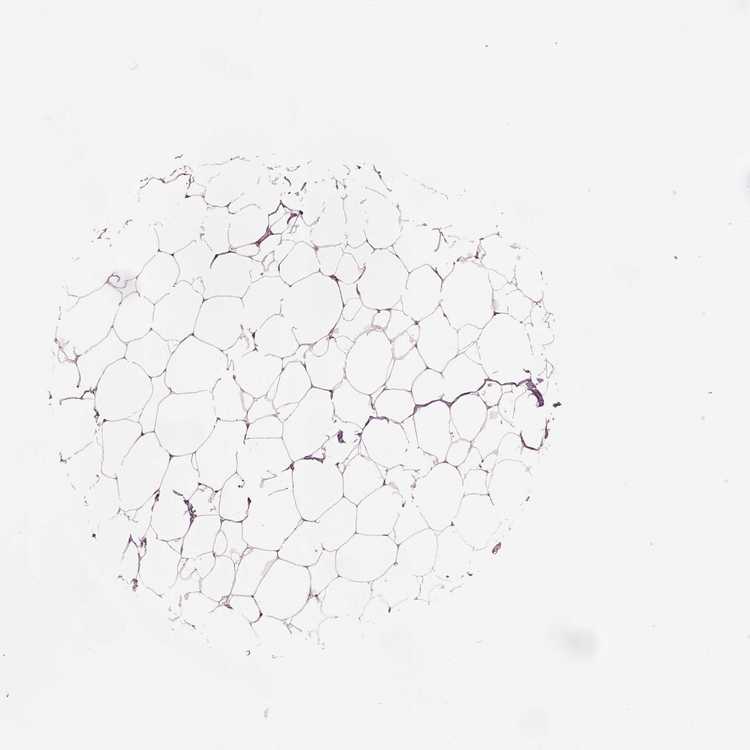

BREAST - Antibody stainingi

Antibody staining in the annotated cell types in the current human tissue is reported as not detected, low, medium, or high, based on conventional immunohistochemistry profiling in selected tissues. This score is based on the combination of the staining intensity and fraction of stained cells.

Each image is clickable and will lead to virtual microscopy that enables deeper exploration of all samples and also displays staining intensity scores, fraction scores and subcellular localization as well as patient and tissue information for each sample.

Antibody HPA019004Antibody HPA073666

Adipocytes Not detectedNot detected

Glandular cells Not detectedLow

Myoepithelial cells Not detectedLow